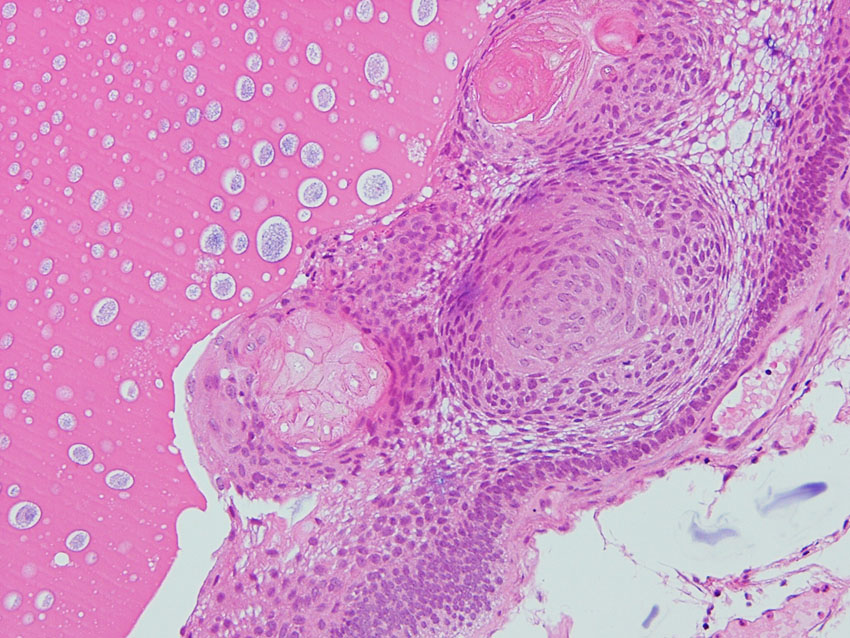

Scarce squamous epithelium with basal vascular network of cyst wall

Adamantinomatous craniopharyngioma showing surface finger (tongue)-like protrusion contains small cysts, wet keratin, and stellate reticulum.